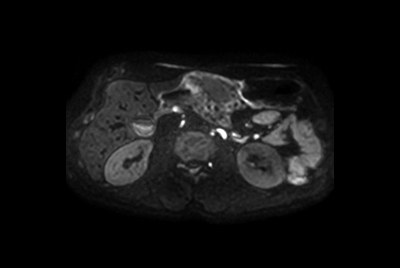

Pancreas nodule – Free breathing